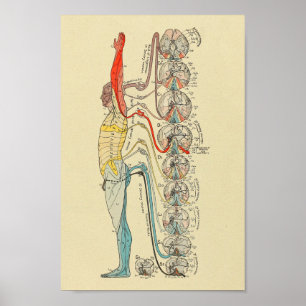

感覚的な神経支配の神経の医学の解剖学の図表 ポスター

価格¥3,350